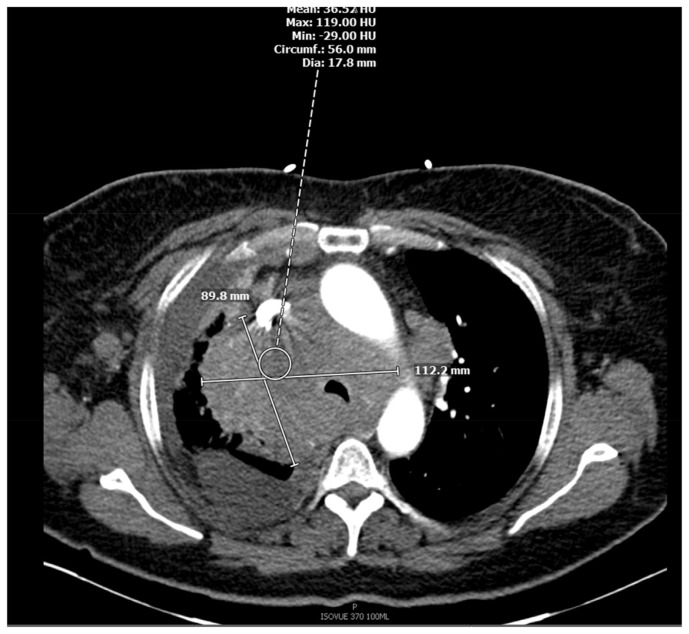

Marginal Zone Lymphoma in a Case of Hidradenitis Suppurativa Treated With Adalimumab Therapy.

Marginal zone lymphoma has seldom been described in relation to adalimumab used for treatment of hidradenitis suppurativa. Although studies have shown an increased risk of lymphoma with adalimumab, most of these studies were done in patients with underlying inflammatory bowel disease or rheumatoid arthritis where the disease itself presents as a confounder for lymphoma. Our case described adds to the role of chronic anti-TNF alpha therapy as a possible etiology of lymphoma.